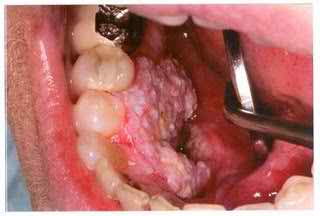

মুখের ক্যানসার এবং আমরা...

মুখের ক্যানসারের লক্ষণ সমুহঃ

১। মুখের ভেতর অলসভাবে পড়ে থাকা ‘Ulcer’ বা ‘ঘা’, যা অনেক দিন ধরে ভালো হচ্ছেনা। এটি খুবই গুরুত্তপূরন।

২। সাদা /লাল, খসখসে ‘ঘা’। যা অনেক দিন ধরে মুখের ভেতর আছে।

সব আলসার বা ‘ঘা’ ক্যানসার নয়। এক্ষেত্রে আক্রান্ত স্থান হতে সম্পূর্ণ বা আংশিক টিস্যু নিয়ে “ Biopsy” পরীক্ষার মাধ্যমে সত্যিই এটি ক্যানসার কিনা নিশ্চিত করা হয়।